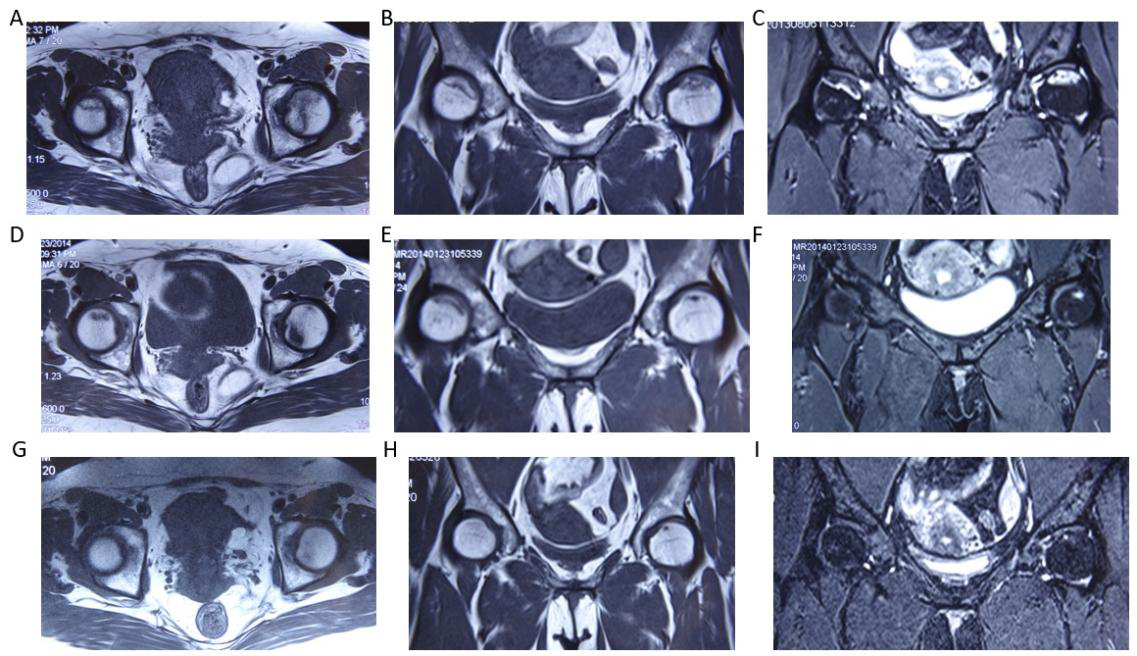

股骨头坏死3期,治疗在MRI上的修复变化

病例,女性49岁,病程3年。A- C:MRI显示双侧股骨头轻度塌陷,双线征,软骨信号消失。D- F:治疗6个月后,明显改善。G-I:治疗1年后,MRI信号正常,恢复正常工作。

A case of stage 3 femoral head necrosis treated with MRI repair changes, female, 49 years old, with a course of 3 years. A - C: MRI shows mild collapse of bilateral femoral heads, double line sign, and disappearance of cartilage signal. D-F: After 6 months of treatment, there was a significant improvement. G-I: After one year of treatment, the MRI signal was normal and normal operation resumed.